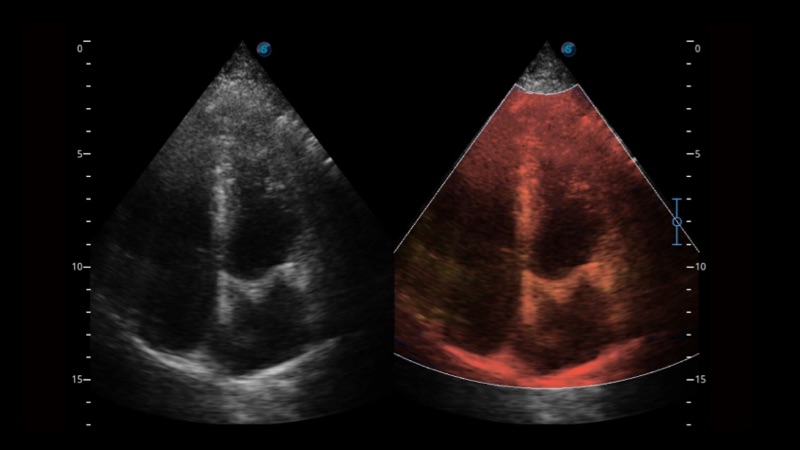

相控阵探头

凭借开立医疗先进的成像技术和优异的探头技术提供的清晰的图像表现,您可以更自信地做出临床决策。